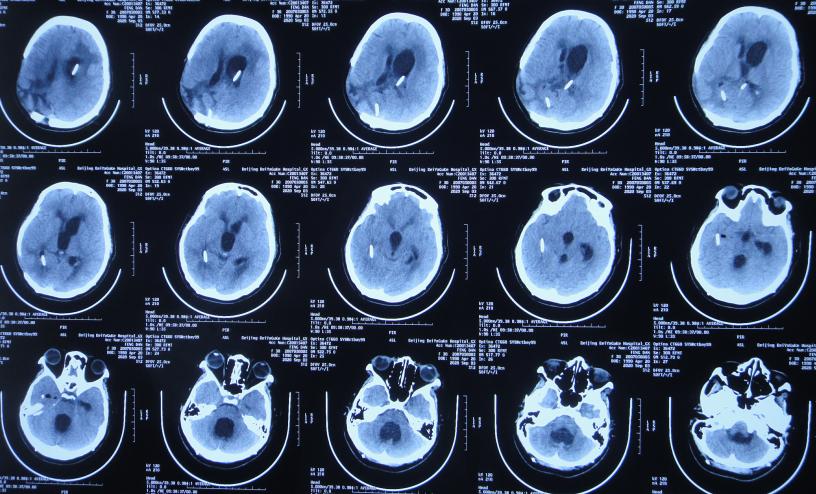

患者于2020年4月2日,在公司上班时突发头痛呕吐,急诊至陕西省西安市某二级医院,急诊查头颅CT检查示右顶叶脑出血破入脑室( 图-1 ),全脑血管造影示脑血管畸形(片子丢失);进行了开颅脑血管畸形切除术+去骨板减压术,术中留置引流外管;术后当天转入ICU继续治疗。

图-1: 2020年4月2日头颅CT